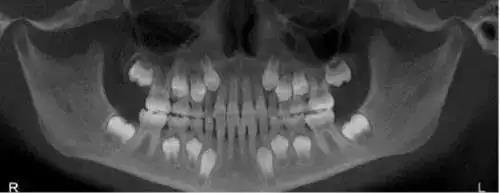

儿童乳牙以下的就是恒牙牙胚

当小朋友还在妈妈肚子里的时候,牙胚就已经发育好了,到了一定的时间,就会自行萌出(男宝宝出牙会比女宝宝晚一点哦)。

所以长牙晚,跟身体缺不缺钙没有关系。美国牙科协会建议,如果宝宝18个月大的时候,还没有长出第一颗牙,就需要就医检查。